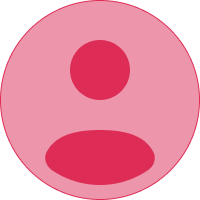

El cuerpo humano

El cuerpo humano